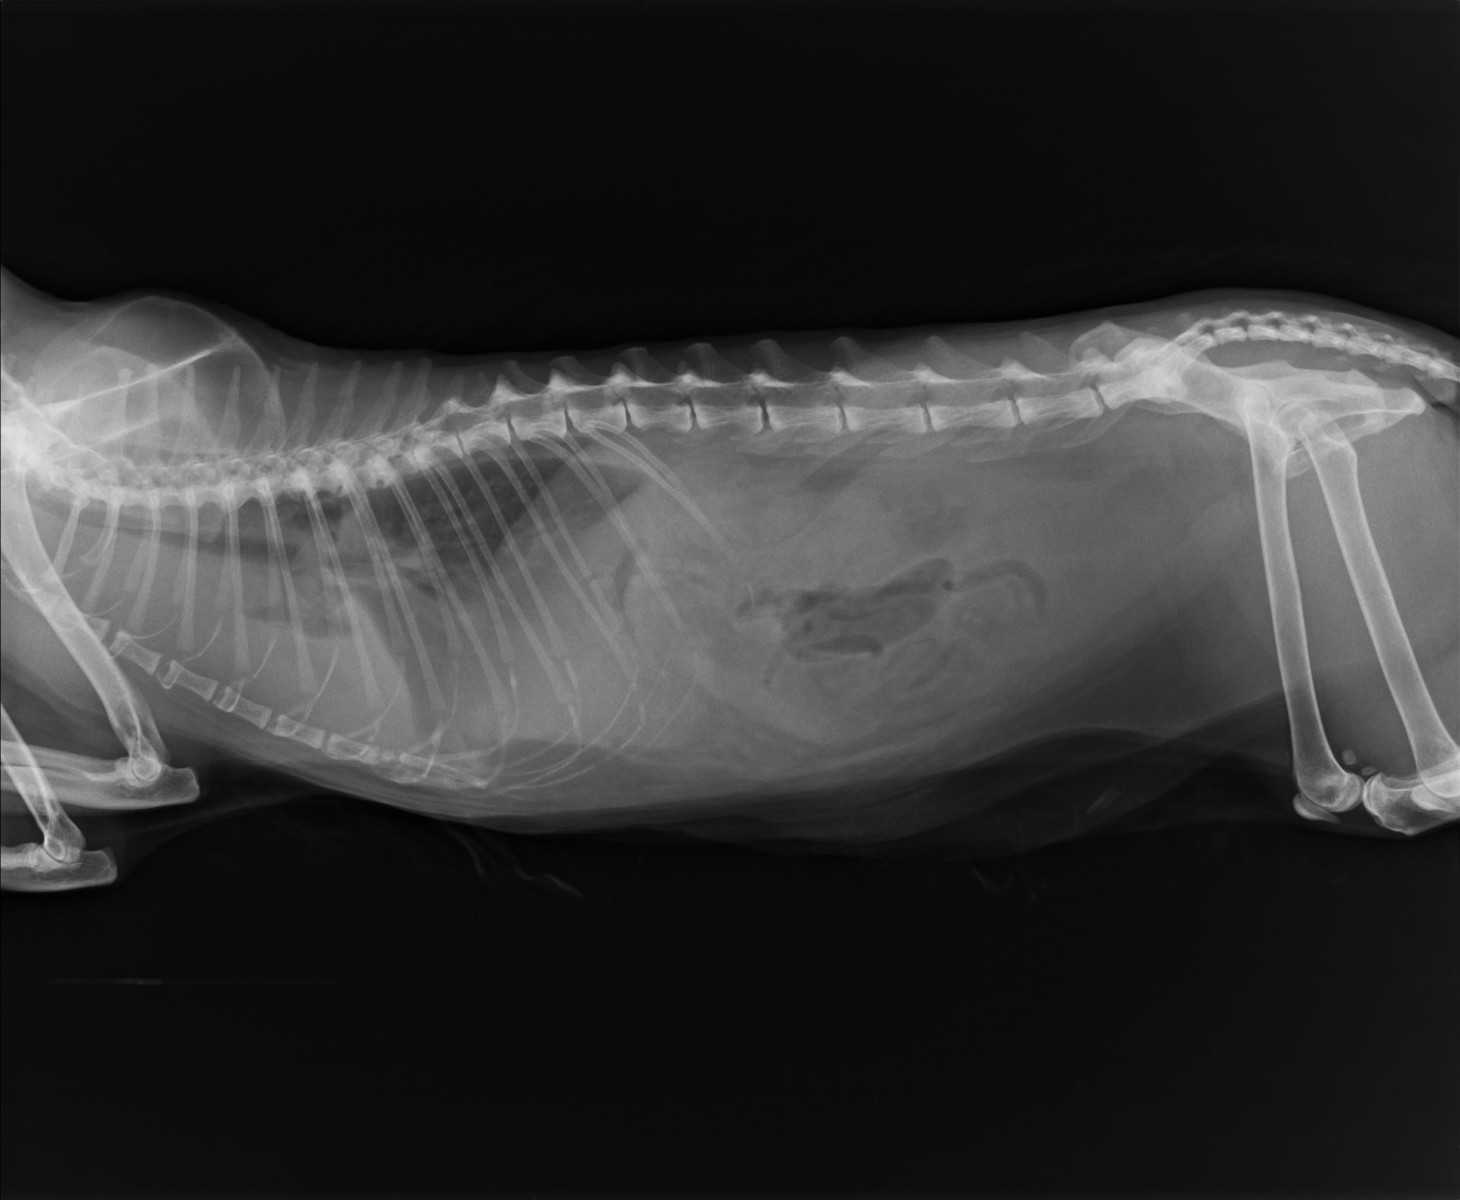

При подозрении на бронхиальную астму необходимо сделать рентгенографический снимок легких. Он нужен не только для подтверждения данного заболевания, но и для исключения других различных патологических изменений, схожих с клинической картиной астмы. Это может быть новообразование или, к примеру, метастазы в легких, кардиологические проблемы, или гидроторакс.

Рис.1. Пред отек легких у кошки при бронхиальной астме.